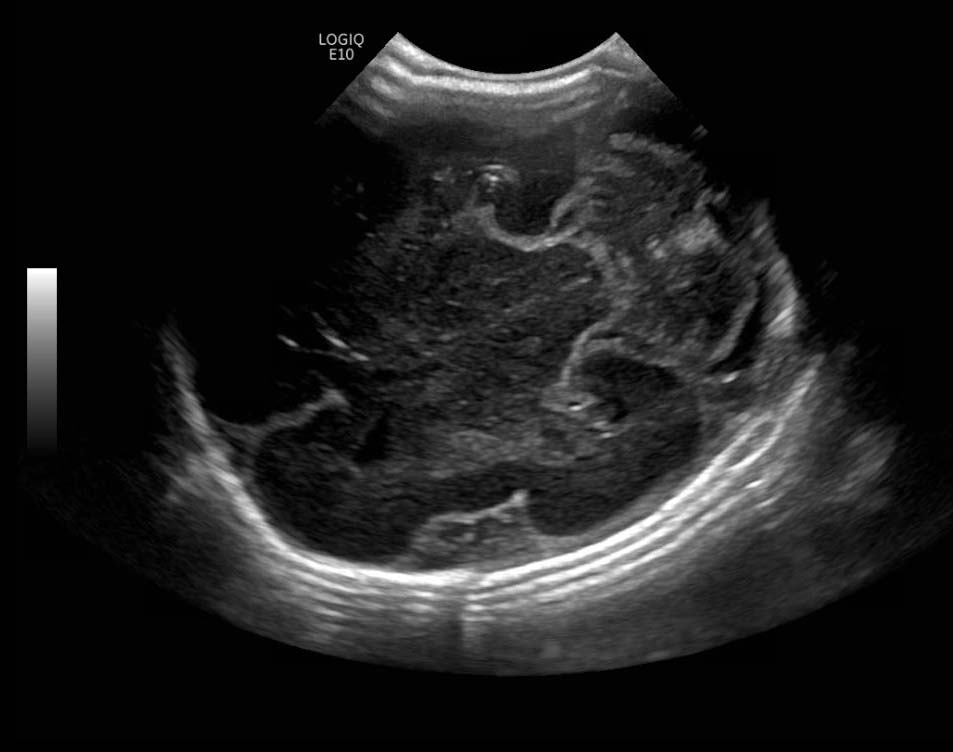

Age: 4 days (born at 24 weeks)

Sex: Male

Indication: Evaluate for germinal matrix hemorrhage

Grade 2 germinal matrix hemorrhage

Sample ReportLeft germinal matrix hemorrhage involving the caudothalamic groove and layering in the occipital horn of the left lateral ventricle without hydrocephalus (grade 2).

No abnormal brain parenchymal echogenicity or extra-axial collections.

Premature sulcation pattern.